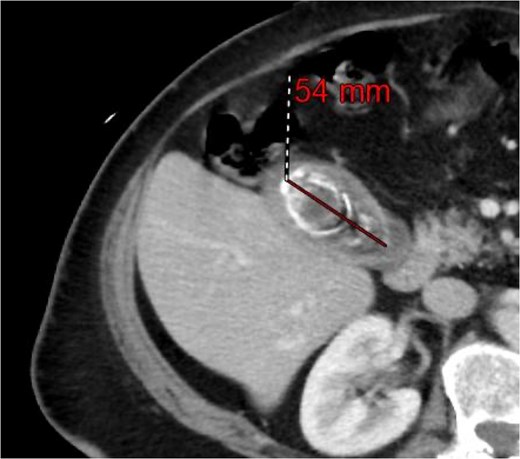

A 63-year-old obese female, known to have hypertension and diabetes, was admitted electively for laparoscopic cholecystectomy and laparoscopic incisional hernia repair with mesh. Prior to surgery, the enhanced computed tomography scan revealed a fat- containing supraumbilical hernia measuring 1.5 cm, a 54 mm gallbladder stone, and unremarkable liver pancreas, spleen, kidneys, and pelvis organs, with no evidence of intra-abdominal free air or fluid (Figs 1 and 2). The patient underwent surgery under general anesthetic using standard sterile procedures. We began with a supraumbilical incision ⁓3 cm above the umbilicus over the previous hernial site. After making a 1 cm longitudinal incision, we identified and opened the fascia, introducing a 12 mm port without immediate complications. The camera was inserted, gas was insufflated, and the abdomen was explored, revealing no immediate injury. An additional 11 mm port was inserted in the left upper quadrant for further exploration. Severe adhesions of the small bowel to the abdominal wall were noted. The first port was examined, and no bowel injury was found. LigaSure was utilized for adhesiolysis, followed by the insertion of two 5 mm ports in the right upper and lower quadrants, and a 5 mm port in the epigastric area. Laparoscopic adhesiolysis was performed, releasing the adhesions without bowel injury. The gallbladder, severely adhered to the liver bed, was identified, retracted cephalad, and Calot’s triangle was achieved. The cystic duct was identified, double clipped, and divided, followed by dissection, clipping, and division of the cystic artery. Intraoperatively, we consulted a senior consultant to confirm the anatomy. The critical view of safety was achieved, and the gallbladder was dissected from its bed. Spillage of gallbladder contents occurred, which was suctioned and controlled. The gallbladder was retrieved through the supraumbilical port using an Endobag without complications (Figs 3 and 4). Hemostasis was secured after examining the liver bed, followed by multiple irrigations and suctioning. The hernial defect was examined and found to be a small incisional hernia (⁓1 × 0.2 cm) containing only fat. After releasing the adhesions, a mesh was applied, tailored to the defect size, and secured with endo-tuckers. Hemostasis was ensured, and a JP drain was inserted under vision and secured with Prolene. All parts were removed under vision, and the skin was closed using clips. The patient tolerated the procedure well and was transferred to the Post Anesthesia Care Unit in stable condition.

Computed tomography of the abdomen and pelvis before the procedure.

Computed tomography of the abdomen and pelvis showing a 54 mm gallbladder stone.